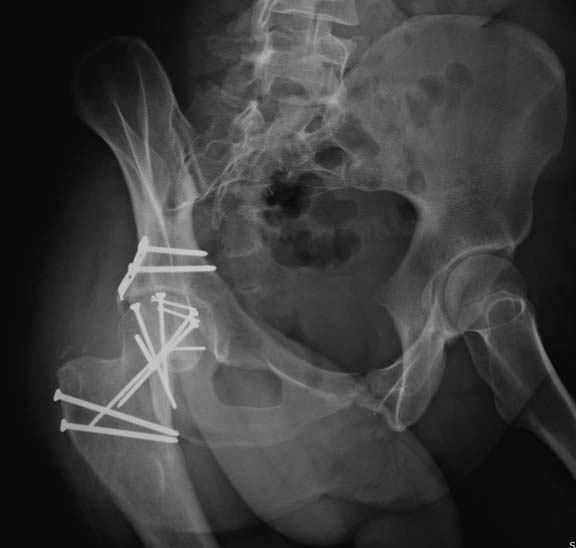

Далее перевод к нам в Травмоцентр и 03.03.2015. через 8 дней операция, выполнен остеосинтез головки 3-мя самокомпрессирующими винтами Autofix под разными углами с погружением в субхондральный слой. Доступ Kocher-Langenbeck с флип-остеотомией большого вертела и задним хирургическим вывихом головки бедра. В полости сустава два свободно-лежачих фрагмента хряща головки, которые были удалены. На снимках виден дефект хряща головки после репозиции. Небольшой фрагмент заднего края фиксирован двумя спонгиозными винтами. Далее шов раны с дренированием. На 2 сутки пациент поворачивался на здоровый бок с валиком между ног, на 4 сутки сидел в кровати и на 6 сутки ходил с помощью костылей.

Насчет разгрузки сустава, после фиксации, нет смысла разгружать аппаратом или другим методом. Движения на второй день на CPM, костыли помогут восстановить слабые абдукторы. Нагрузку через 3 недели можно разрешить при расположении фрагмента в нижнем, вне зоны нагрузки, а в нагрузочной зоне только через 12 недель!

Здесь выбрана правильная тактика и операция сделано на хорошо. Надеюсь, промах с фиксацией не создаст проблему. Можно было добавить в задную стенку spring plate и винты до медиального кортекса в фиксации вертела.

Здесь клинические примеры: Первый случай передний доступ, второй с ICP monitor Flipp Trochanteris

и с переломом заднего края.